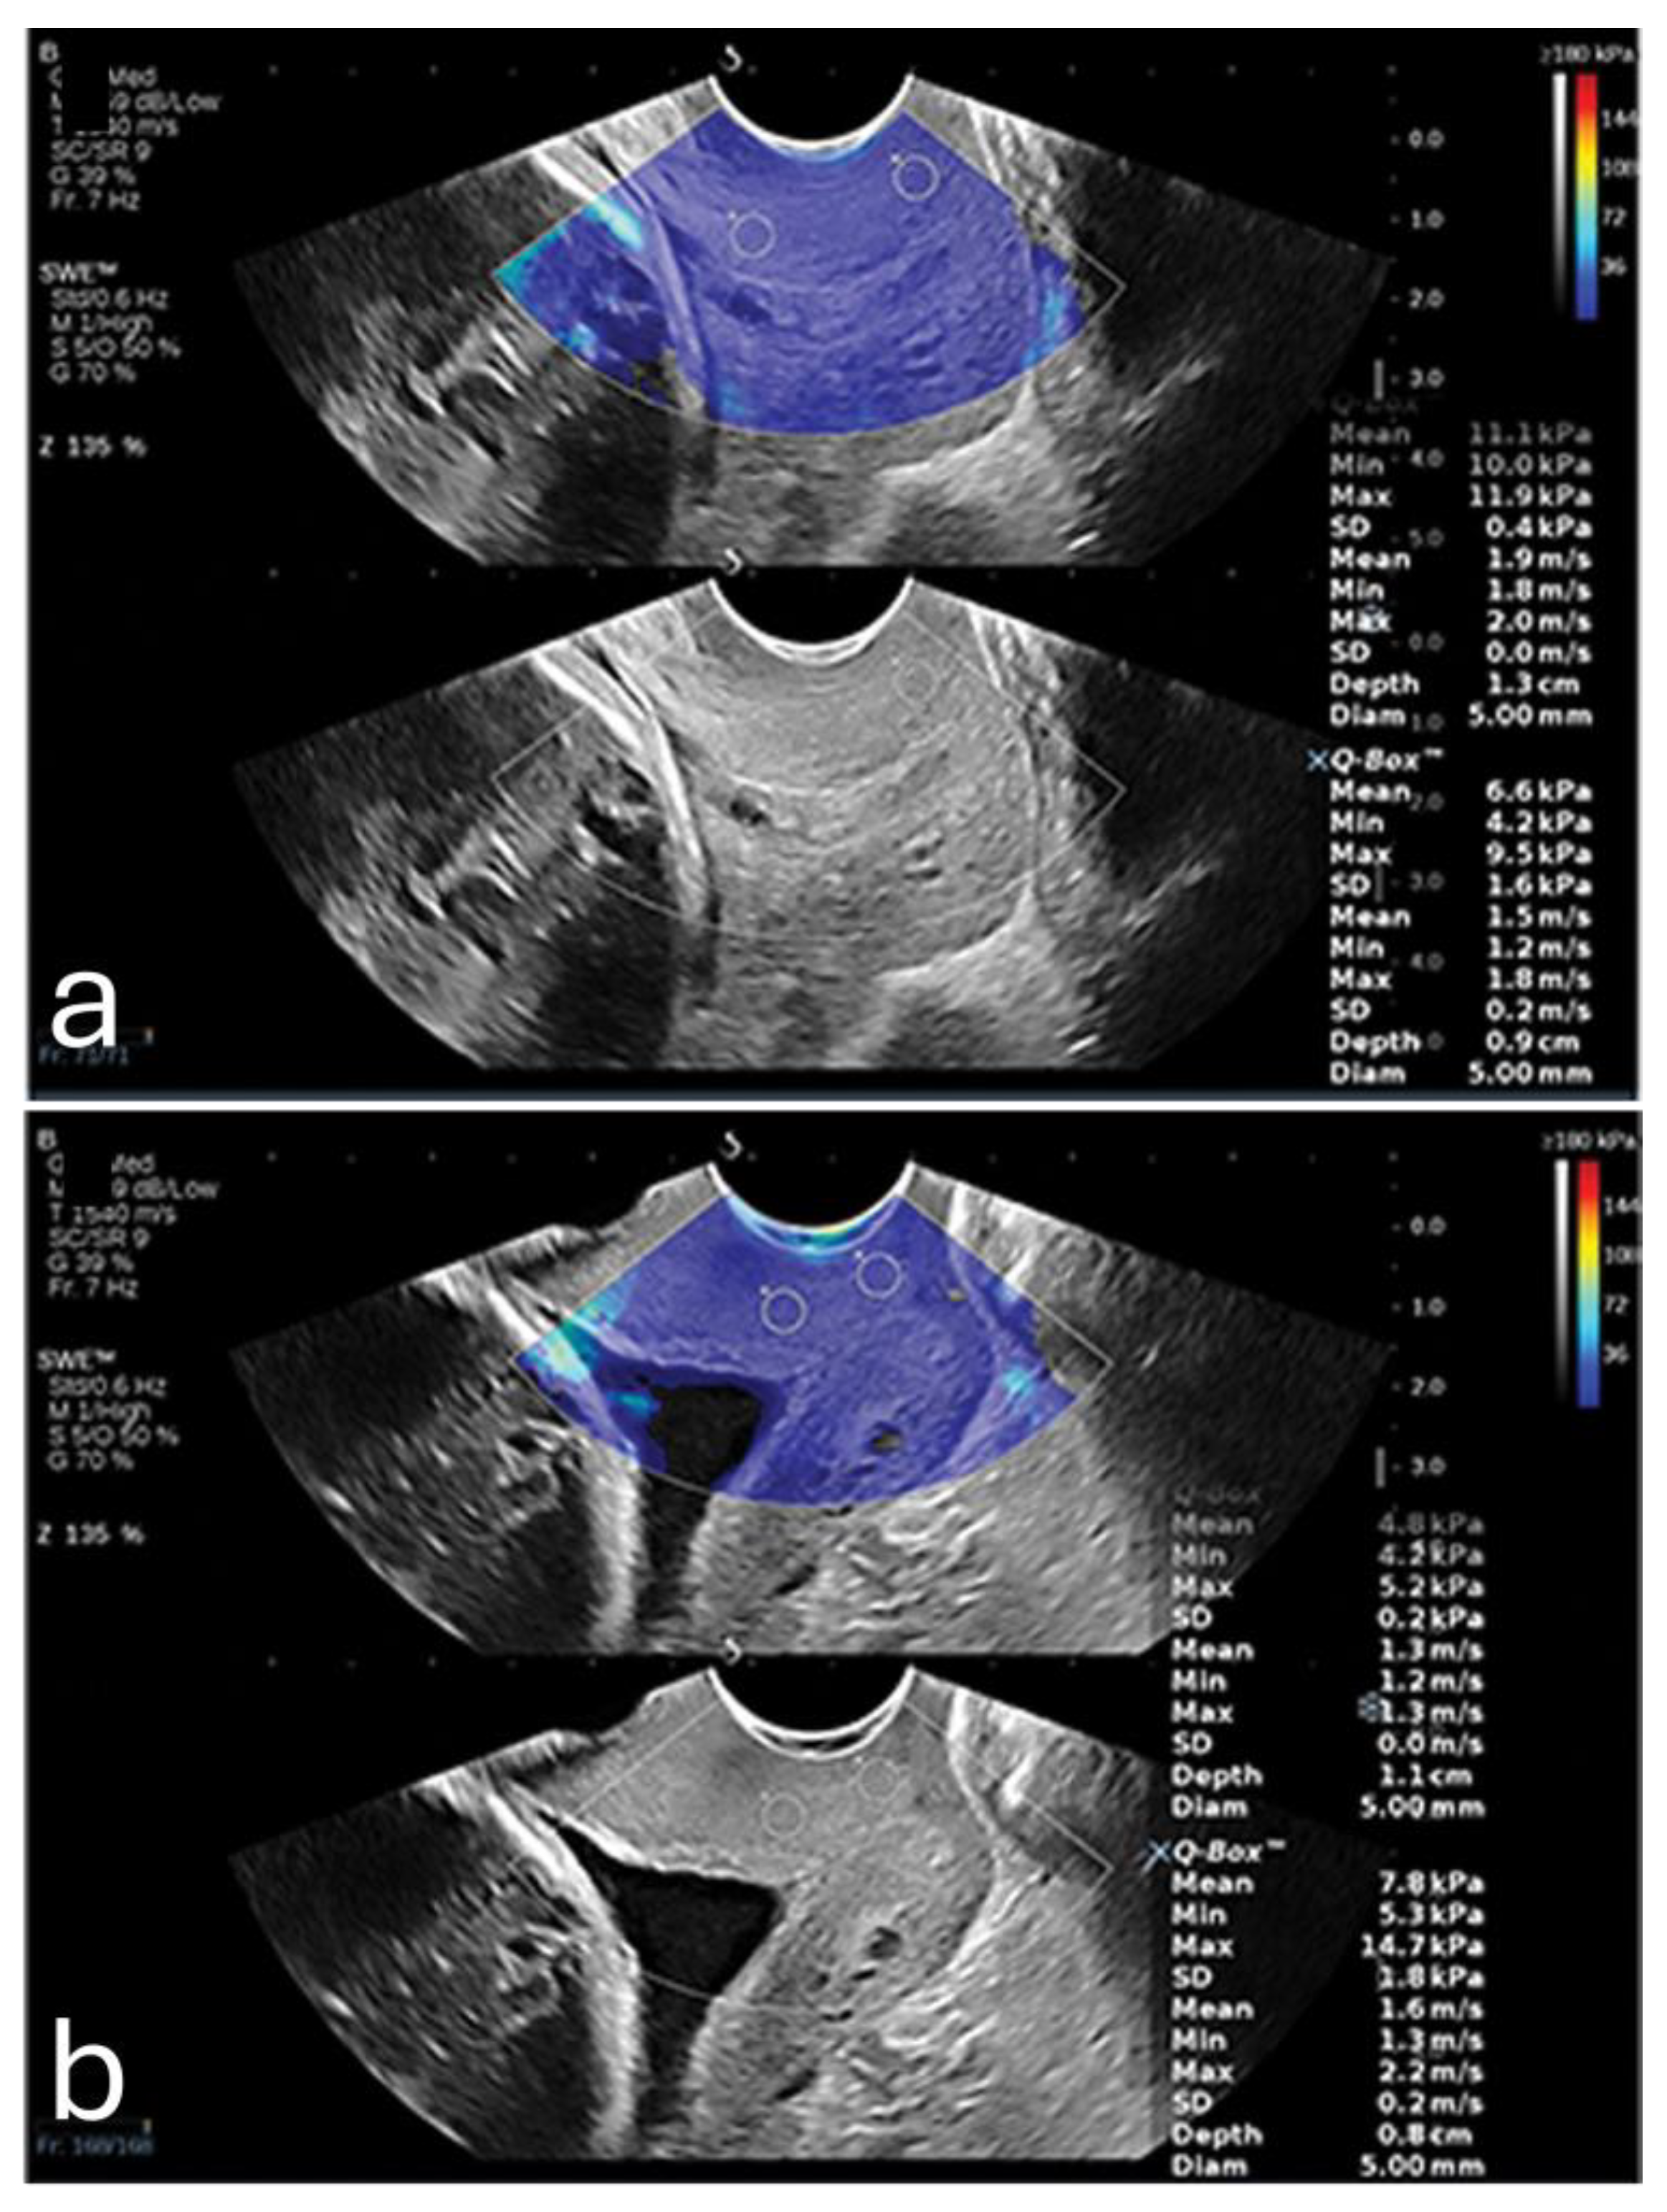

One of the primary factors influencing placental elasticity is the layered arrangement of the chorionic villi, which are densely populated with capillaries and responsible for mediating maternal-fetal nutrient transfer. As trophoblastic cells invade and remodel maternal spiral arteries early in pregnancy, the placental vascular network expands, allowing the tissue to maintain elasticity and accommodate increased blood flow. This vascular adaptation not only supports fetal needs but also underpins the biomechanical softness that elastographic assessments detect in healthy placentas [36]. This softness becomes altered in cases of placenta percreta, where the placenta becomes significantly stiffer (Figure 2) [37].

Figure 2. A pregnant woman with placenta percreta (a) showing increased average shear wave velocity (1.95 m/s) in comparison to a pregnant woman with normal placenta showing normal average shear wave velocity (1.83 m/s). Reproduced with permission from Sage. © 2024.